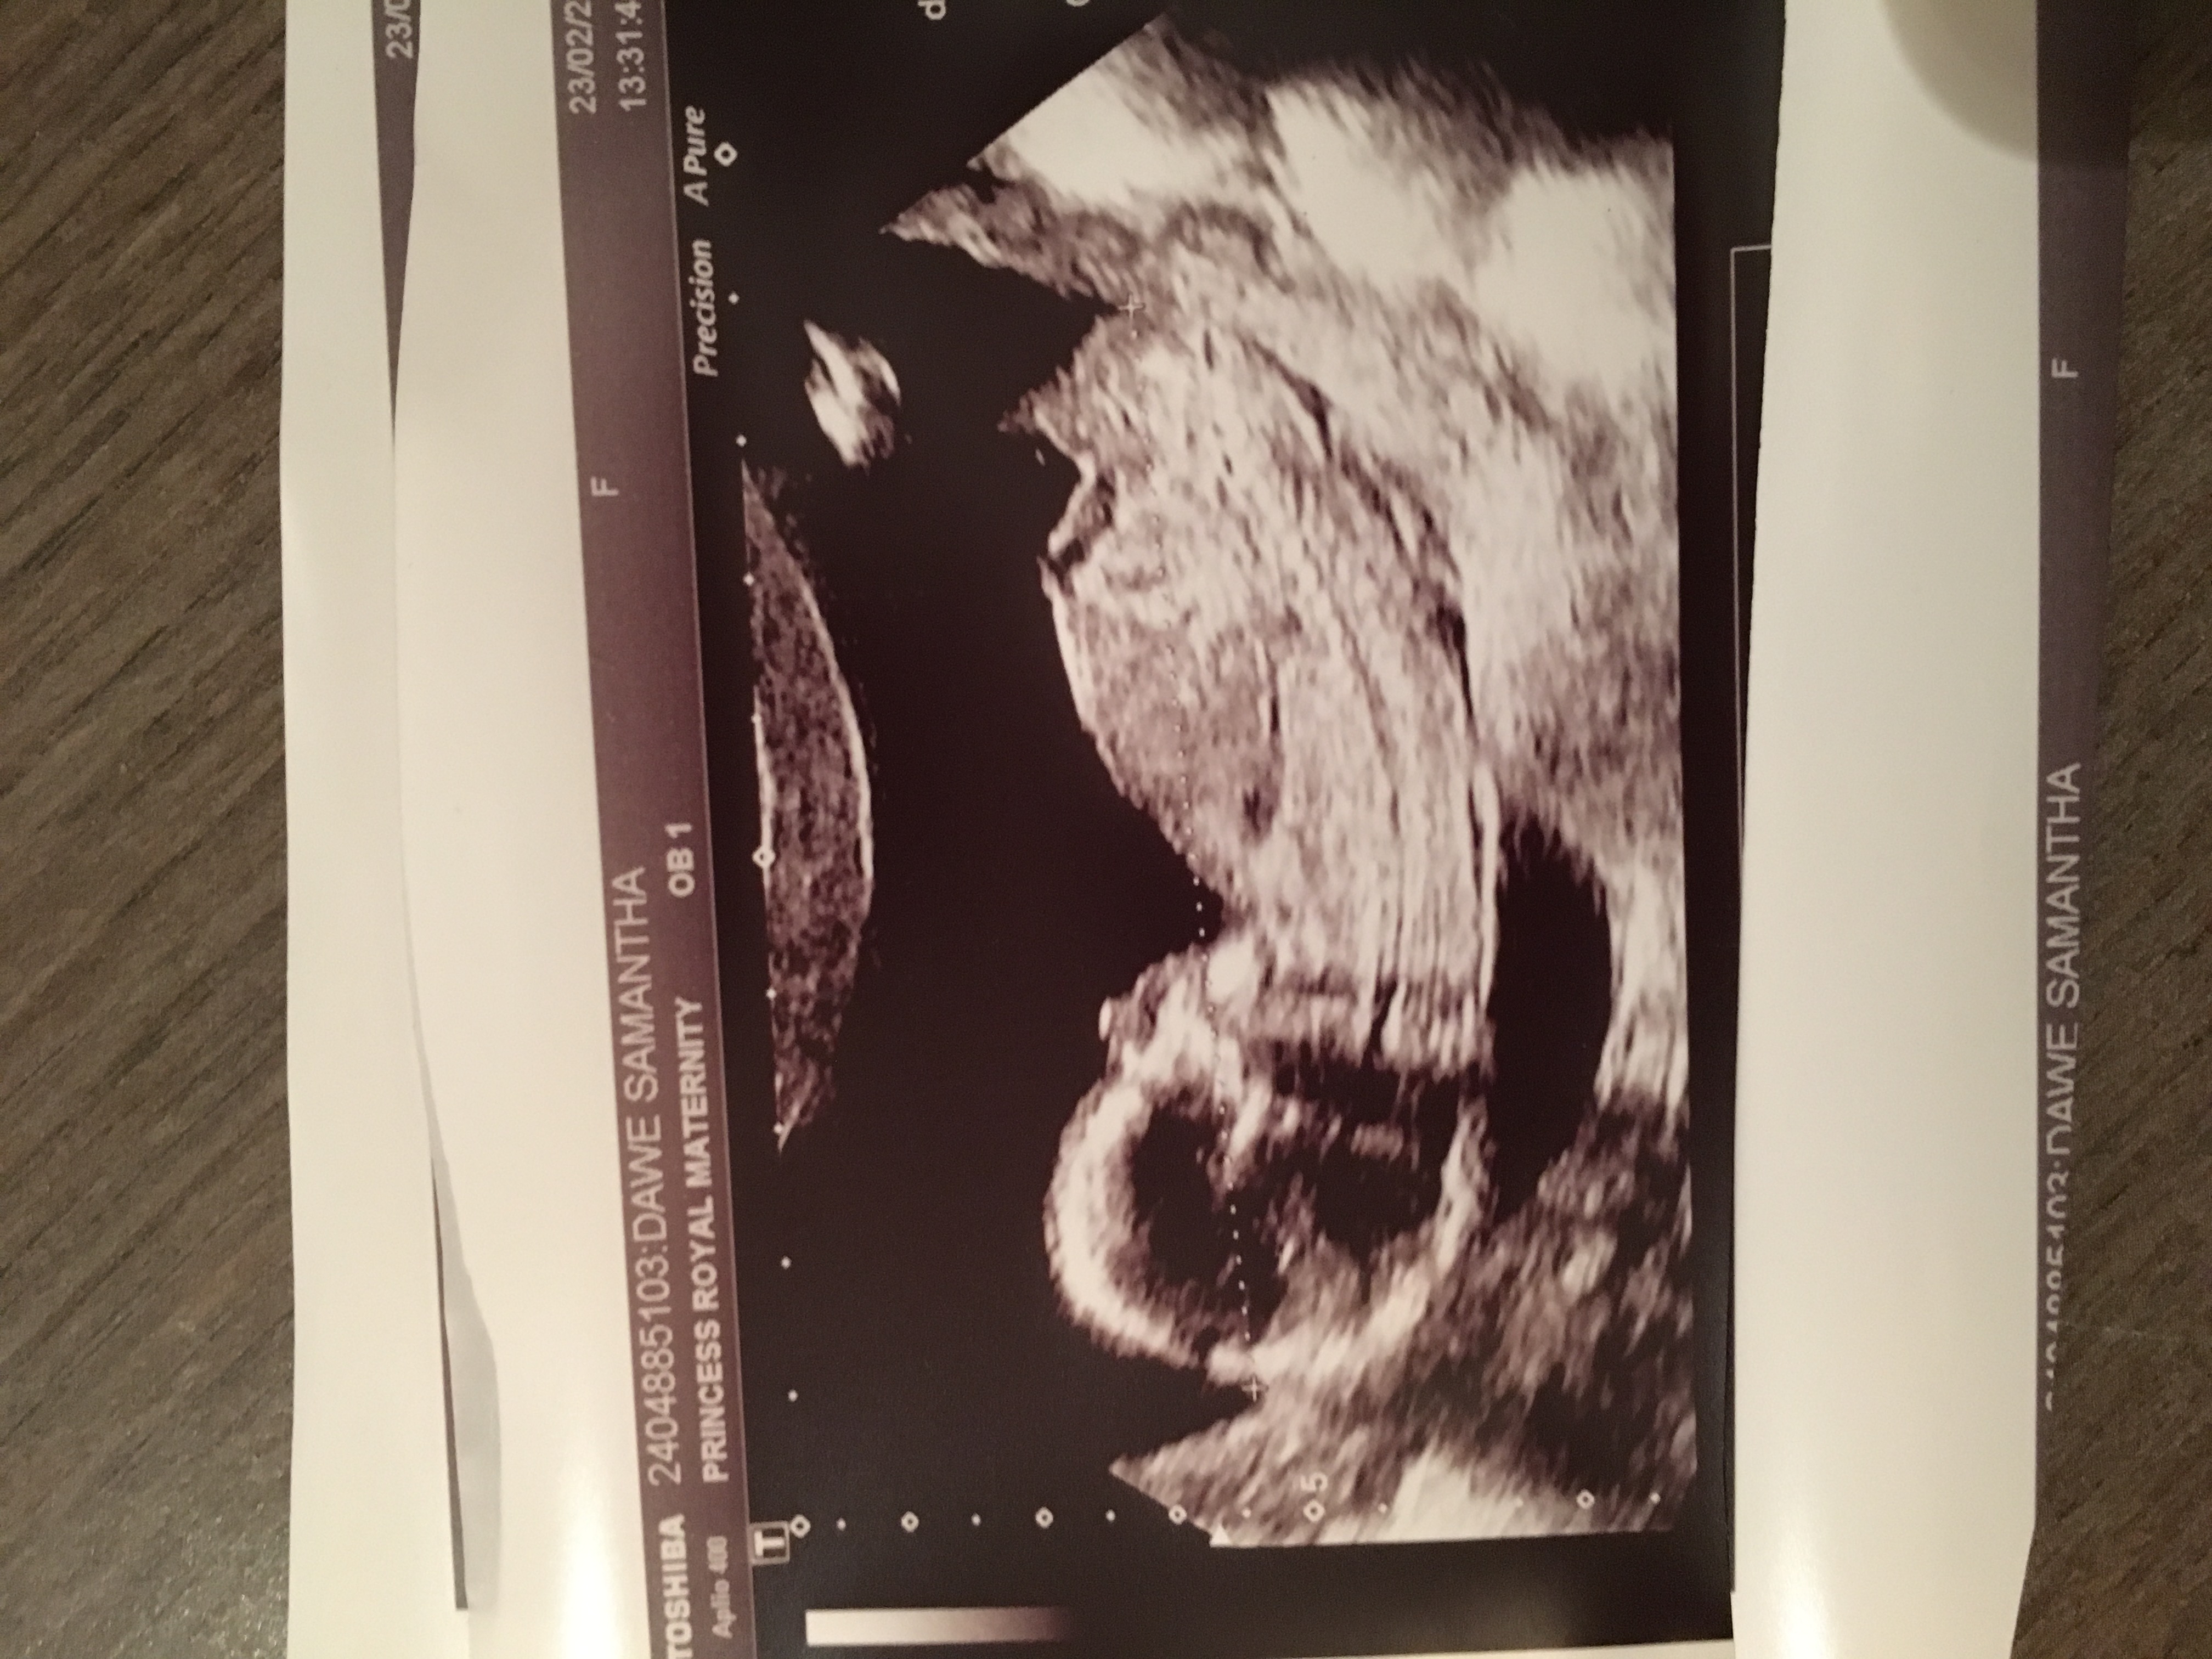

No nub here, more pics?

Attachment 35121

Tricky, maybe boy, but not sure. Any video?